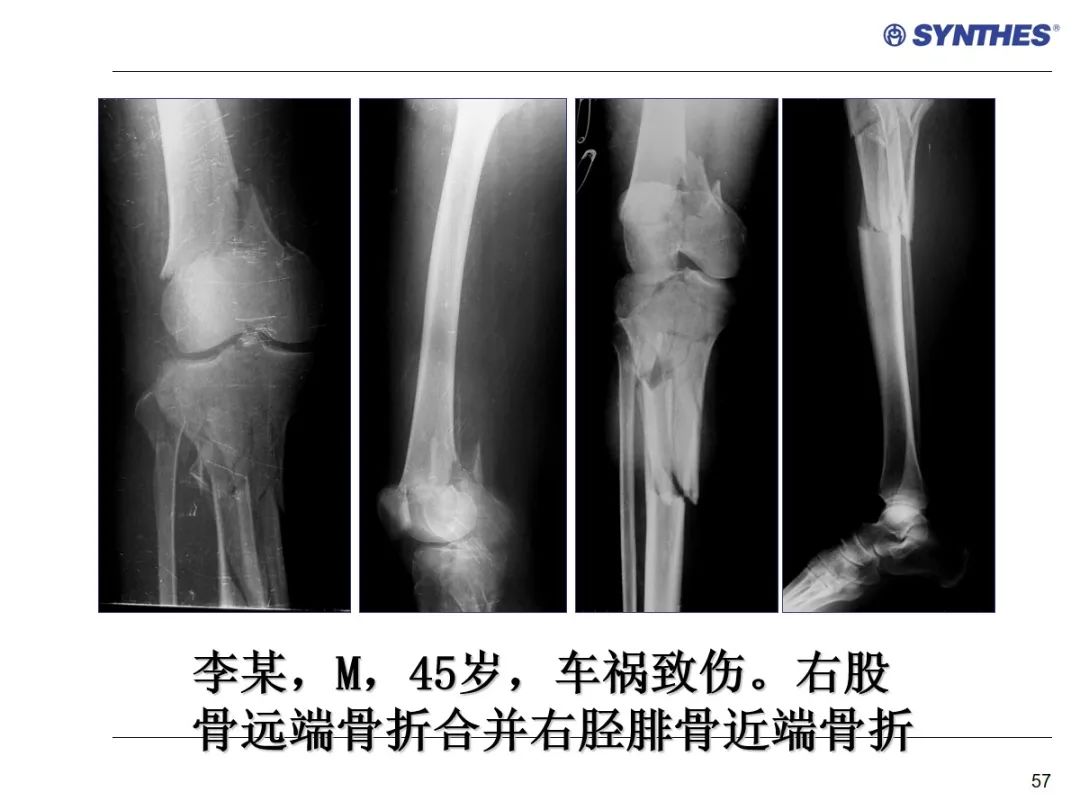

LISS微创固定系统应用技巧,原来如此简单!